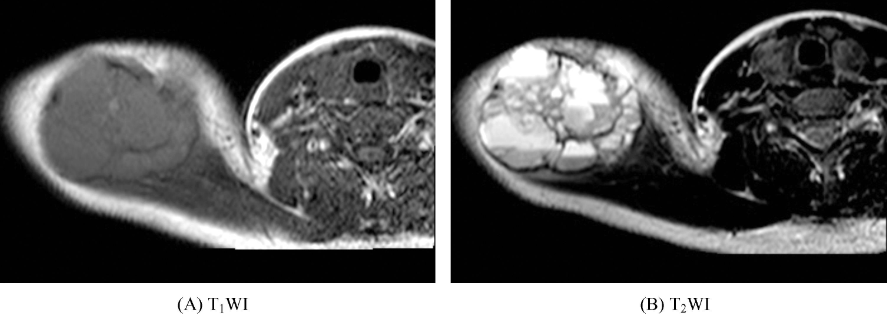

十一、动脉瘤样骨囊肿

好发于长骨干骺端,表现为囊状膨胀性骨破坏,骨壳菲薄,病变与正常骨交界区可见低信号硬化环,病变内可见多个含液囊腔,并可见液-液平面。囊腔间隔为软组织信号,并可见钙化和(或)骨化(图11)。增强扫描间隔强化。

图11 动脉瘤样骨囊肿